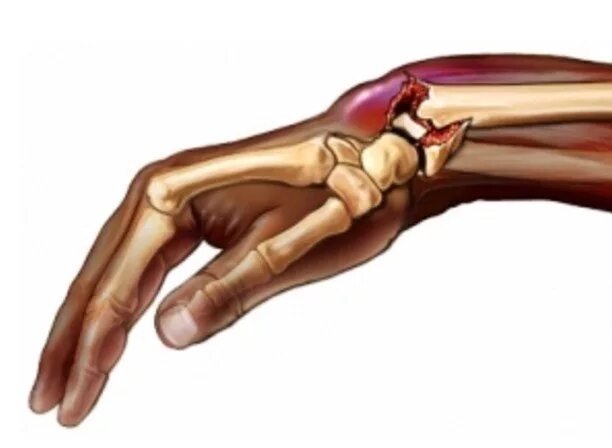

Перелом лучезапястного сустава мкб 10